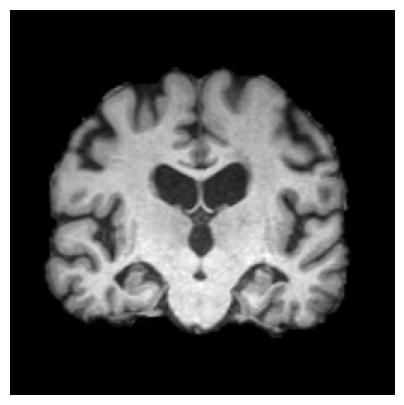

4.3.2 ADNI

We consider two groups constructed from the ADNI dataset based on hippocampal volume, a well-established neuroimaging biomarker of Alzheimer’s disease–related neurodegeneration. Each group includes 918 2D slices. Subjects exhibiting reduced hippocampal volume indicative of hippocampal atrophy are assigned to Group 1, while subjects with preserved hippocampal volume form Group 2. This stratification induces group differences associated with disease-relevant anatomical variation and provides a clinically meaningful setting for evaluating whether the proposed feature-level explanations highlight brain regions known to be implicated in Alzheimer’s disease/cognitive impairment.

We use a ResNet-50 encoder pretrained on the UK Biobank dataset, predicting the age of brains, and adapt this pretrained model using a linear probing strategy on the ADNI dataset. Specifically, we train a logistic regression layer on top of the frozen encoder to predict group membership, while keeping all encoder parameters fixed. After training, the linear head is discarded, and the frozen encoder is used to extract embeddings for two-sample testing and for generating feature-level explanations. We apply the proposed feature-level explanation method to individual MRI scans and assess whether the resulting attributions align with known disease-related neuroanatomical patterns.

Results.

Figure 7 indicates the qualitative results. Our explainability method consistently highlights the hippocampal and medial temporal lobe regions, and the resulting heatmaps show strong correspondence with areas affected by hippocampal atrophy. These results supports that the identified regions align with established AD biomarkers.